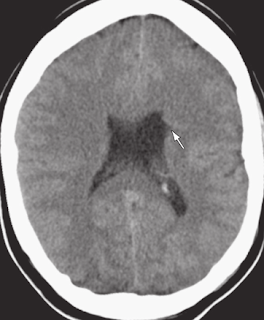

The patient is a 16-year-old boy with seizures.

Axial CT scan demonstrates a deep gray matter–lined (arrowheads) cleft extending from the pia of the overlying cerebral cortex to the ependymal lining of the ventricle.

At a slightly caudal level, axial CT scan demonstrates a slight outpouching or “nipple” (arrow) along the ependymal surface of the cleft. Diagnosis: Closed-lip schizencephaly.